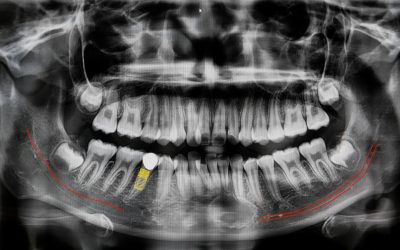

TAC Cone Beam dentale: l’esame 3D fondamentale per la diagnosi odontoiatrica

La TC Cone Beam è un’indagine radiologica tridimensionale che consente una valutazione dettagliata del cavo orale, permettendo di analizzare con precisione altezza, larghezza e spessore dell’osso, oltre alle caratteristiche anatomiche degli elementi dentali. Grazie all’elevata accuratezza diagnostica e a una dose di radiazioni inferiore rispetto alla TAC tradizionale, è ampiamente utilizzata in odontoiatria, in particolare in chirurgia orale e implantologia, per la pianificazione di interventi complessi. Le sue applicazioni si estendono anche ad altre branche come ortodonzia, endodonzia e parodontologia, rendendola uno strumento fondamentale per una diagnosi completa e personalizzata.